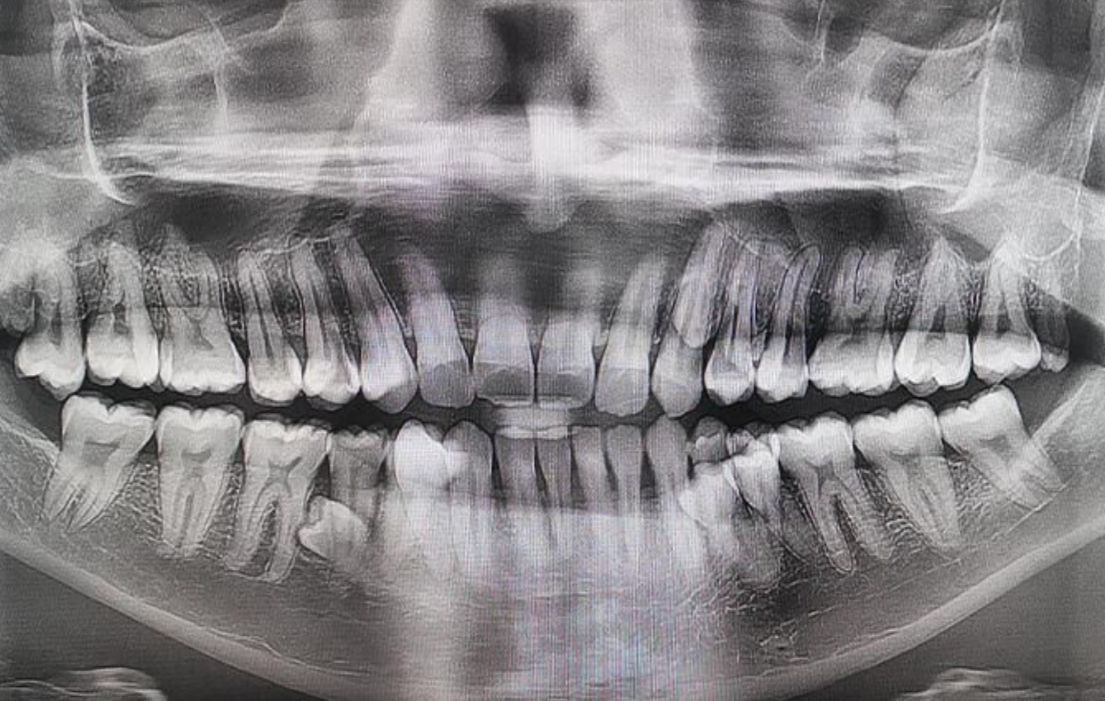

一名馬來西亞男子因擁有多達42顆牙齒,成功獲得健力士世界紀錄認證,成為「世上擁有最多牙齒的人」,比一般成年人多出足足10顆!

其後接受牙科檢查時,X光片顯示仍有4顆牙齒尚未完全長出。直至2023年初,穆尼亞迪確認自己總共擁有42顆牙齒,並正式打破世界紀錄。他形容情況相當罕見,但幸運的是,多數牙齒排列整齊,亦未引發任何健康併發症。

穆尼亞迪指出,額外的牙齒並未對他的日常生活造成困擾,甚至在他主動提起前,大部分人都未有察覺異樣。「每當我說出自己比一般人多10顆牙齒時,大家都感到十分驚訝,很多人一開始都難以相信,畢竟普通人通常只有32顆牙齒。」